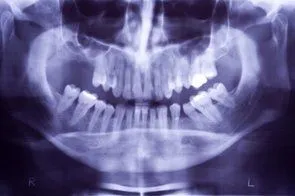

Loss of posterior teeth may result in excessive forces being placed on your remaining teeth.  Fortunately, the use of dental implants and crowns allow you to replace these missing teeth.  However, the position of the sinus in the upper posterior areas may be too low for proper placement of dental implants.

A simple procedure allows the sinus floor to be repositioned, creating enough space to properly place an implant.  Various grafting materials are used to encourage your bone to grow more quickly into the area, helping to stabilize the dental implant. Replace with your own bone in this area the grafting material as it grows into the area.

Under certain conditions, an even simpler procedure can be utilized.  When possible, the bone remaining under the sinus floor is gently “pushed up”, thus lifting the floor of the “dropped” sinus.  Bone replacement materials are then placed beneath this lifted bone.  Once again the bone materials are replaced as your body grow new bone into this area.

Sinus augmentation procedures are highly predictable, with studies reporting over 95% success.  Following sufficient healing of a sinus augmentation (6-10 months), implants are placed in a predictable and successful manner.  It is important to realize that if the sinus augmentation procedure does not result in enough bone for implant placement, additional bone may be regenerated through a second sinus augmentation procedure at the time of implant placement.